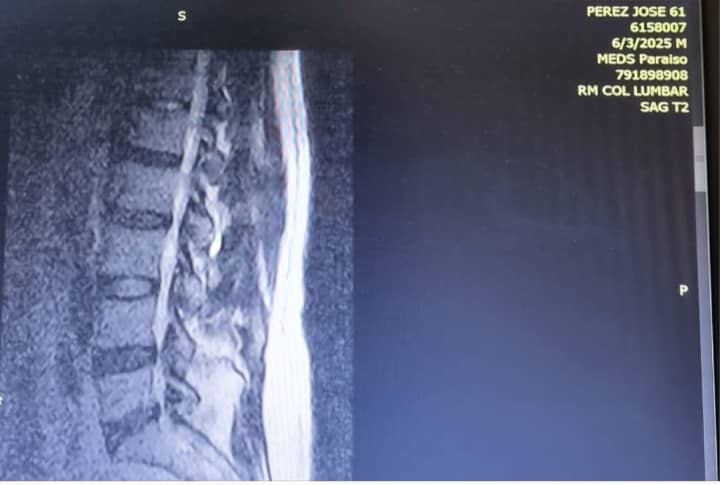

Es un placer saludarte, mi nombre es José Rafael Perez venezolano de 62 años de edad. Mucho sabré agradecer que hagas un alto en tu día a día para conocer mi situación, me encuentro impedido para movilizarse por una protusion de disco lumbar L4/L5 y L/5-S1.

Debo someterne a una cirugía a la mayor brevedad posible: Disectomia + foraminotomia y fusión L4 -S1